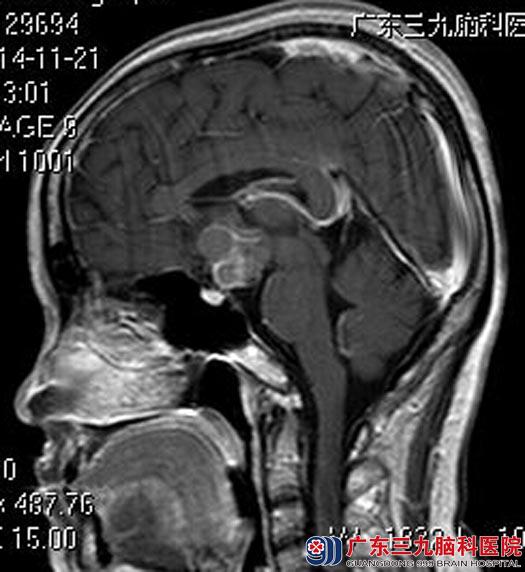

近三个月来出现双眼视物模糊,后枕部头痛,伴有多饮多尿,当地医院头颅CT检查提示颅内鞍区病变。广东三九脑科医院进一步头颅MR检查提示:鞍上池内见一类圆形囊实性占位性病变,大小约24.4mm×28.8mm×27.5mm,考虑颅咽管瘤可能性大。

手术前